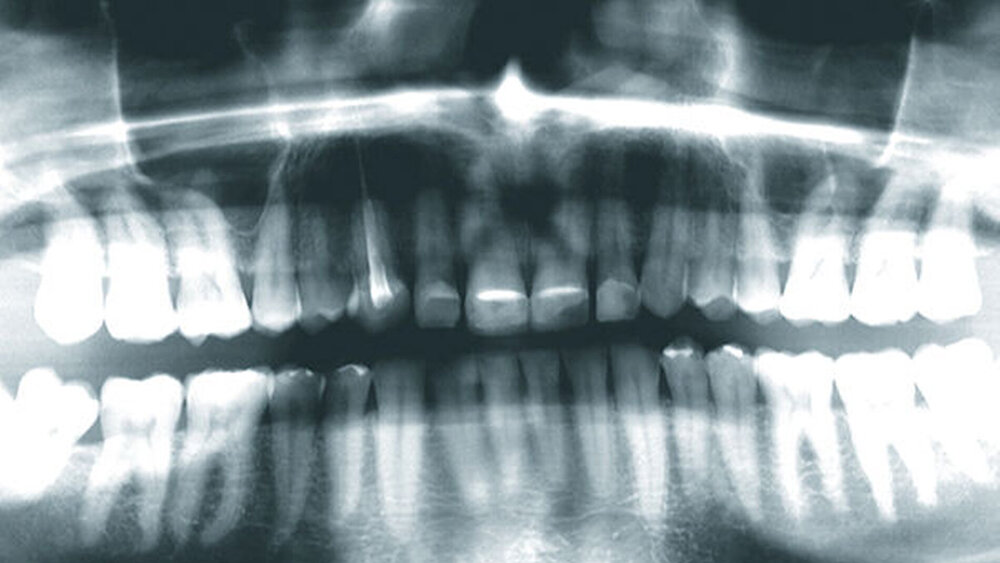

2015 stellte sich ein 47 Jahre alter Mann mit Schmerzen im TMG (Temporomandibulargelenk) vor. Er hatte außerdem ein ästhetisches Anliegen, da ein Stück vom Veneer eines mittleren oberen Schneidezahns abgebrochen war (Abb. 1–3). Die klinische und radiografische Analyse (Abb. 4) ergab einen Verlust der Bisshöhe und der Zahnsubstanz aufgrund von Bruxismus.

Digitale intraorale Fotos wurden aus der Vorderansicht unter Retraktion sowie aus der Okklusions- und lateralen Ansicht erstellt. Zudem wurden mit einer digitalen Spiegelreflexkamera (DSLR) zusätzliche Fotos erstellt (frontal, lateral und 45º). Eine diagnostische Abformung beider Kiefer wurde mit einem intraoralen Scanner (Carestream 3500) durchgeführt. Die maximale Interkuspidationsposition (MIP) wurde intraoral mit dem intraoralen Scanner Carestream 3500 erfasst, und die neue Vertikaldimension der Okklusion (VDO) wurde durch entsprechend weites Öffnen des virtuellen Artikulators in der CAD/CAM-Software (CAD/CAM = computergestützte Konstruktion und Fertigung) erreicht.